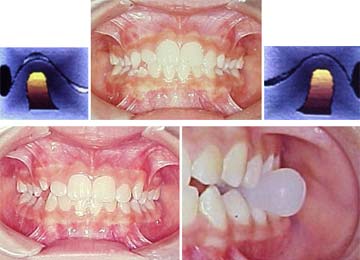

Em nossa técnica, executaremos expansão lenta: bilateral nos casos de mordida cruzada funcional, e expansão unilateral dirigida nos casos de mordida cruzada verdadeira ambas com ativação 3 x por semana, lembrando que após a expansão e recondicionamento oclusal através de exercícios específicos com hiperbolóide (instrumento de mastigação), não haverá necessidade de contenção.

Adicionamos também o fato das cápsulas de acrílico serem excelentes desprogramadores de postura errada, facilitando após a expansão, nos casos de mordida cruzada funcional uma rápida reposturação mandibular, uma vez que a placa de acrílico deve simular um equilíbrio através da mordida funcional em miocêntrica(10).

Isto é conseguido observando a linha média dentária do paciente quando este abre a boca, que deve coincidir com a linha média facial (observar os freios labiais). Fechando a boca, haverá um ponto onde há o reflexo neuropostural defensivo do trauma oclusal de topo, que leva a mandíbula para o lado de trabalho, criando um desvio no final do movimento. É este desvio que anularemos quando montamos a placa em miocêntrica, simulando um equilíbrio postural funcional, sem travamentos. Quando isto não ocorre de forma natural poderemos utilizar as aletas funcionais Gomes(4) ou Aleta Valter, que são recursos como barreiras de acrílico, adicionados na vestibular do aparelho, no lado de trabalho como que conduzindo a mandíbula para uma relação cêntrica e ao mesmo tempo afastando a influência compressiva do bucinador sobre a maxila. Este recurso adicional agiliza a reorganização postural e vem melhorando ainda mais nossa técnica. Não obstante, após o descruzamento deveremos eliminar a aleta unilateral e promover a bilateralidade, entrando agora com exercícios de mioterapia, através do hiperbolóide que é um instrumento de mastigação, veremos o efeito desta arma terapêutica em nossa casuística.

Para concluir este tema apresentaremos, como exemplo, um caso simples de mordida cruzada postural, desencadeada por respiração bucal em decorrência de uma rinite alérgica, a qual foi logo diagnosticada e convenientemente tratada. Observaremos também as prováveis implicações nas articulações temporomandibulares, estimuladas pelo uso do hiperbolóide com intuito de reprogramar o sistema estomatognático.